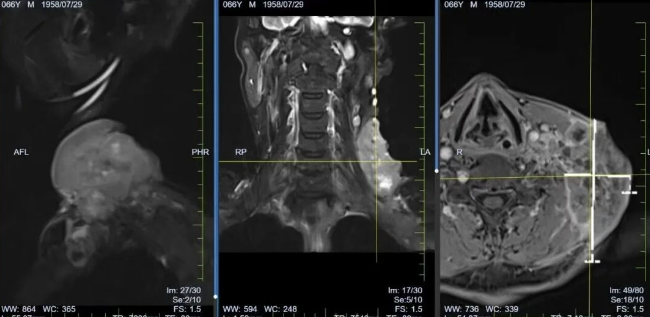

“刚开始还担心治疗副作用,没想到医护人员早有准备。” 李先生说,治疗期间出现的轻微恶心、乏力,都在医护团队的针对性护理下得到缓解。更让他惊喜的是,开始治疗后,颈部肿块开始迅速缩小,治疗6个月结束复查时,影像学检查显示,原本 8×10cm 的肿块已完全消失,食管梗阻症状也明显减轻。

*患者颈部肿块治疗后